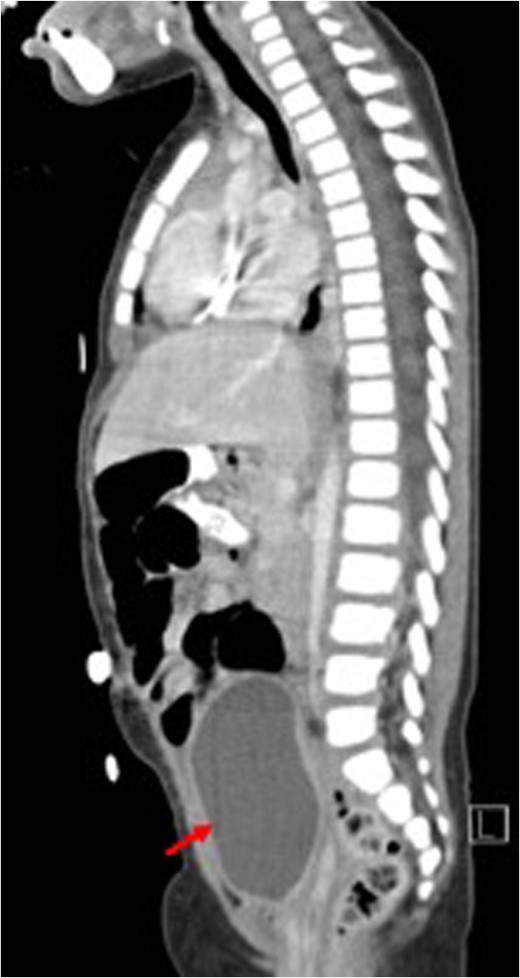

Before treatment sagittal view (CT) showing a large mass (white arrow) compressing on bladder (red arrow).